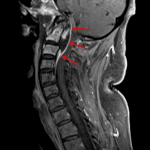

- Erosive changes along the ventral surface of the clivus

- Lytic changes in the anterior aspect of the C2 vertebral body with adjacent nasopharyngeal soft tissue edema and enhancement

Erosive changes along the ventral surface of the clivus and lytic changes in the anterior aspect of the C2 vertebral body raise concern for associated osteomyelitis. Adjacent nasopharyngeal soft tissue edema and enhancement, which can also be further evaluated for abscess on C spine MRI.